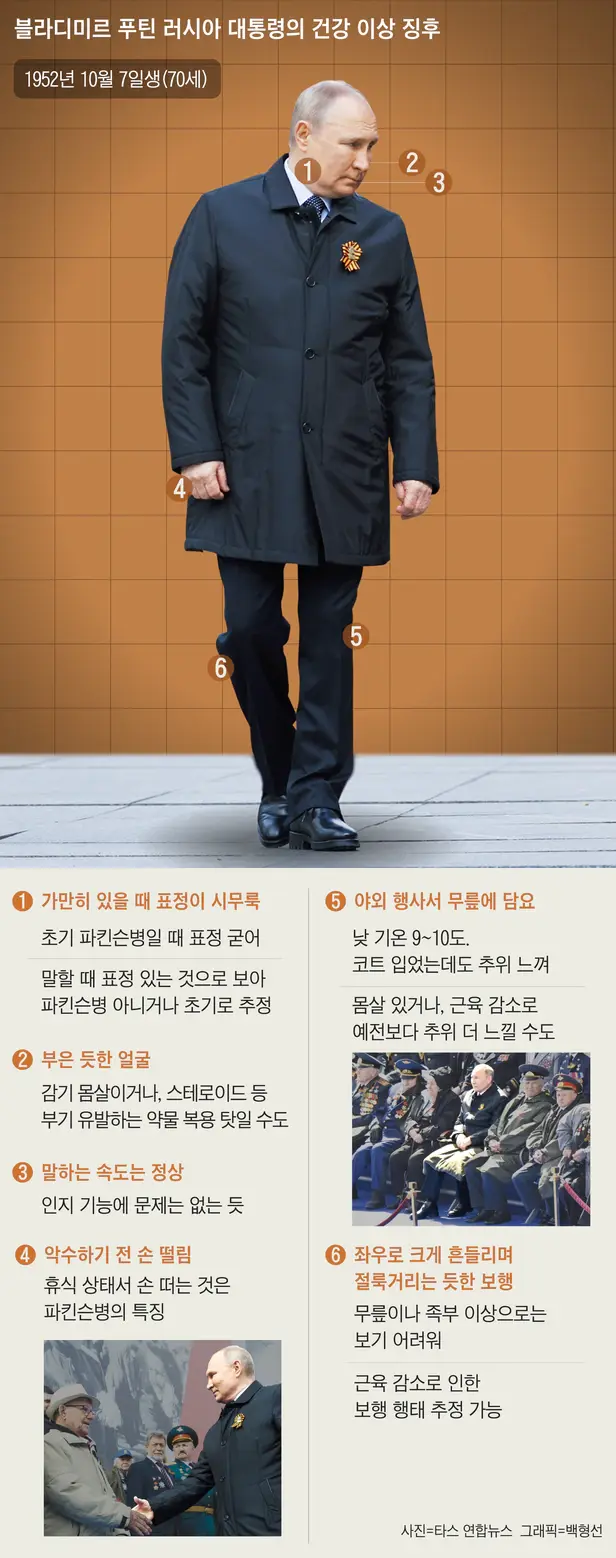

최근 푸틴 대통령의 건강이상증세들이

포착되었다고 하는데,

이러한 증후들에게서 '초기 파킨슨병'의

가능성 여부를 의심해 볼 수 있다고 합니다.

'파킨슨병' 증상은?

파킨슨병의 증상으로는

운동증상과 비운동 증상으로

나타날 수 있는데요.

운동 증상으로는 떨림 증상이 있습니다.

가장 눈에 잘 띄는 증상이라고 할 수 있는데요.

주로 편하게 앉아 있거나 누워있을 때

나타나게 되며 손, 다리를 움직이게 되면

사라지게 됩니다.

두번째 증상은 경직인데요.

파킨슨병 초기에는 근육이 뻣뻣하게 느껴지게

되는데 그래서 근육이나 관절의 문제로

착각하실 수도 있습니다.

파킨슨병이 서서히 진행되면서

근육이 조이거나 통증이 느껴지기도 합니다.

부위에 따라 허리나 두통,

다리 통증을 호소하는 경우도 있습니다.

세번째는 서동인데요.

'서동'은 행동이 느려지는 것을 의미합니다.

글씨를 쓰는 등의 미세한 움직임이

둔해지고 눈의 깜빡임이나 표정, 자세를

변경하는 등의 동작 횟수도 눈에띄게

감소합니다.

대부분 환자 본인은 증상을 잘 알지 못합니다.

그 외 평상시 자세를 유지하지 못하며,

구부정한 자세, 걷는 것에 대한 두려움을

느끼실 수 있겠습니다.